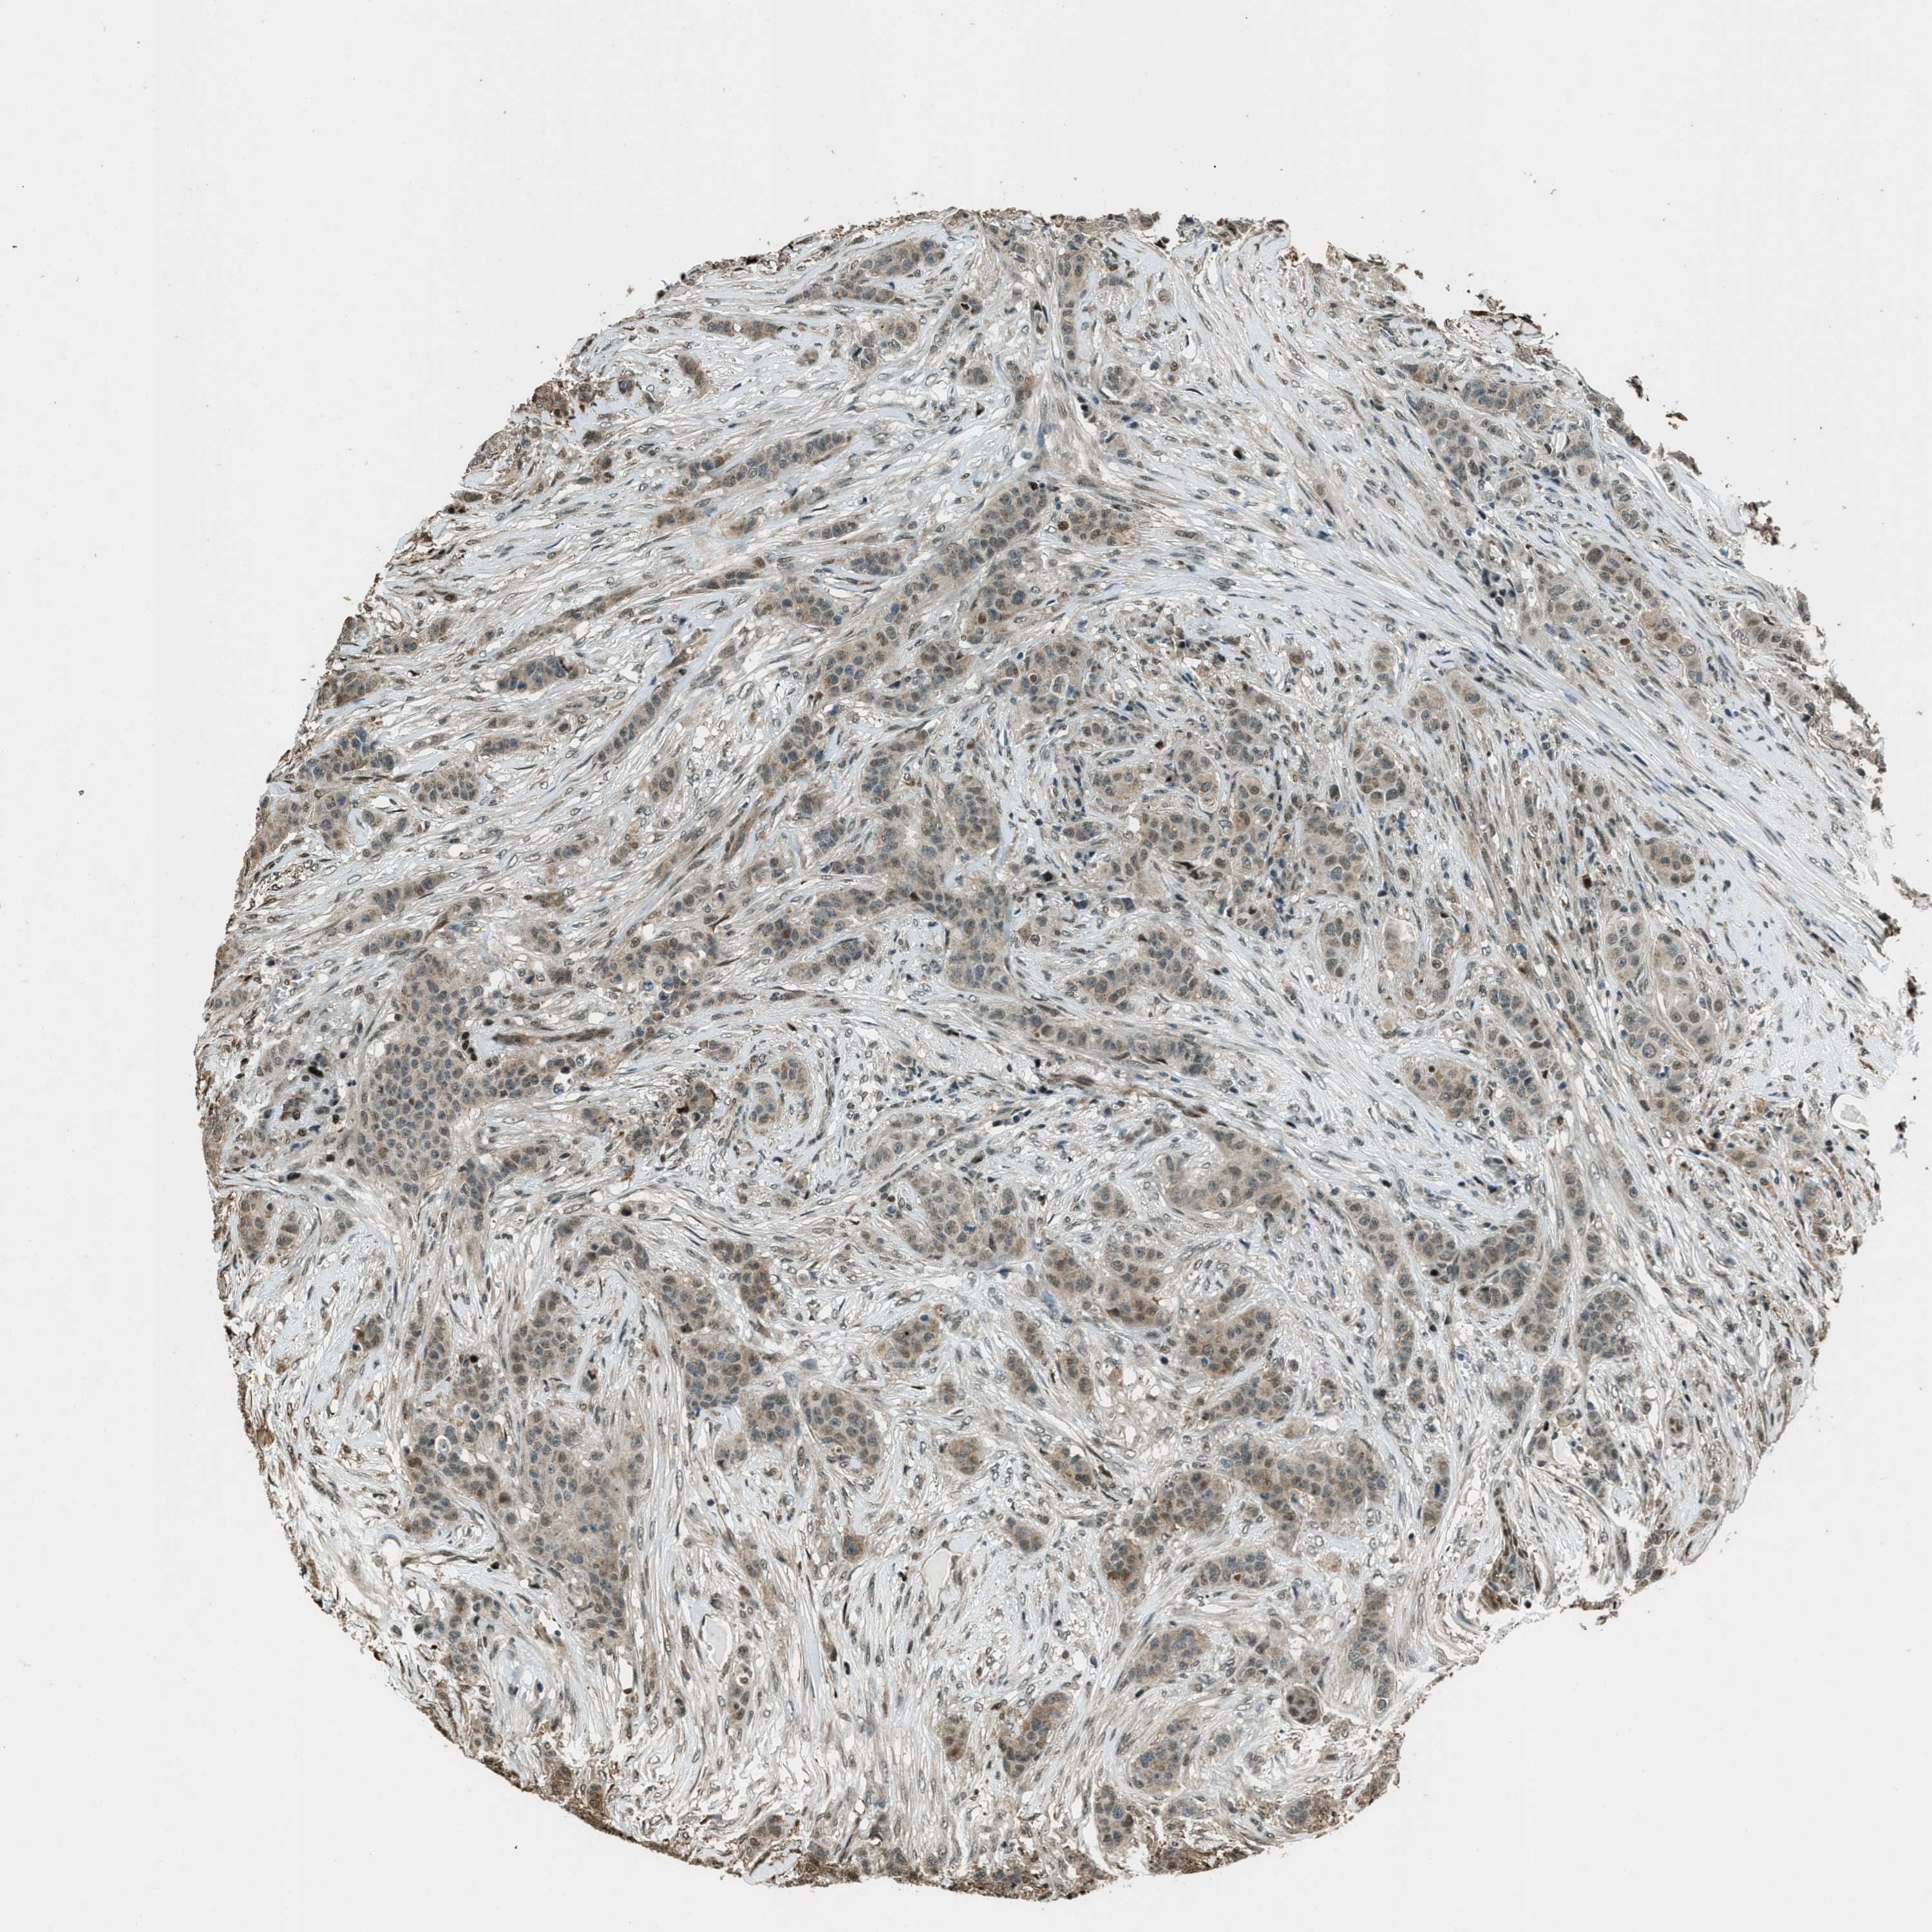

CANCER BREAST CANCER Show tissue menu

Breast cancer

Human cancer

TARDBP is not prognostic in Breast Invasive Carcinoma (TCGA)